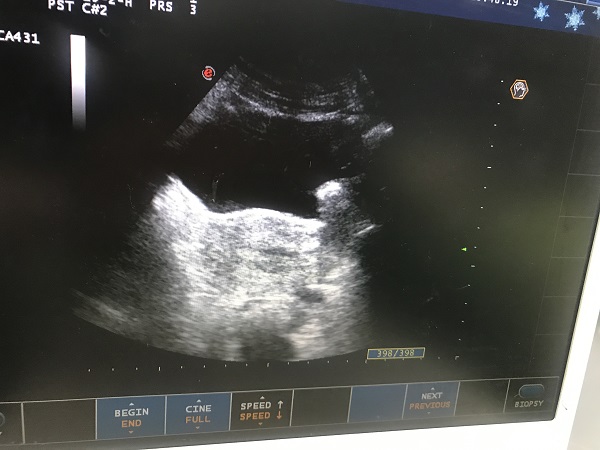

近日,總醫(yī)院婦科團(tuán)隊(duì)成功為一位II型宮角妊娠患者實(shí)施了腹腔鏡監(jiān)測下負(fù)壓吸宮術(shù)。II型宮角妊娠是一種少見的異位妊娠,妊娠囊向?qū)m腔外擴(kuò)展生長使宮角膨脹外凸,一旦破裂可發(fā)生致命的大出血,需于妊娠早期終止妊娠。由于患者強(qiáng)烈要求保留子宮完整,經(jīng)婦科手術(shù)團(tuán)隊(duì)充分討論,在麻醉科和功能檢查科的全力支持配合下,婦科為患者行腹腔鏡監(jiān)護(hù)下負(fù)壓吸宮術(shù)。手術(shù)過程順利,術(shù)后床旁B超顯示宮腔內(nèi)無明顯異常回聲,復(fù)查血液指標(biāo)良好,患者非常滿意。